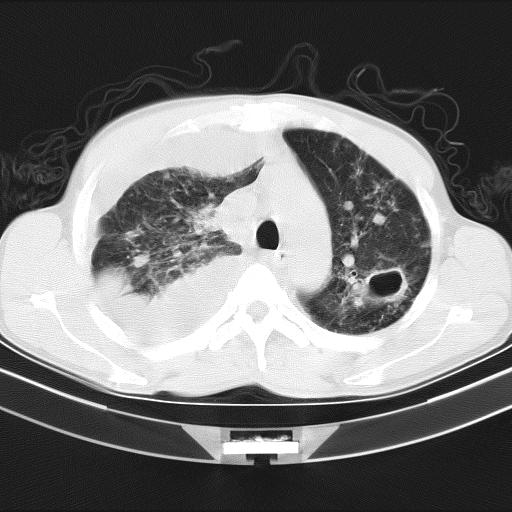

男性,44岁,结核病史多年。现胸闷气短,咳嗽,偶咳血。

右侧胸腔积液

右肺下叶不张

双肺多发结节影最分空洞形成考虑占位不除外结核

双肺陈旧性病变

1、右侧大量胸腔积液伴右肺压缩性膨胀不全,建议抽液治疗后复查 2、两肺继发性tb伴空洞形成。

1)两肺继发性肺结核伴空洞形成,左肺多发性结核球。2)右侧大量胸腔积液伴右肺部分膨胀不全。3)纵隔淋巴结肿大。